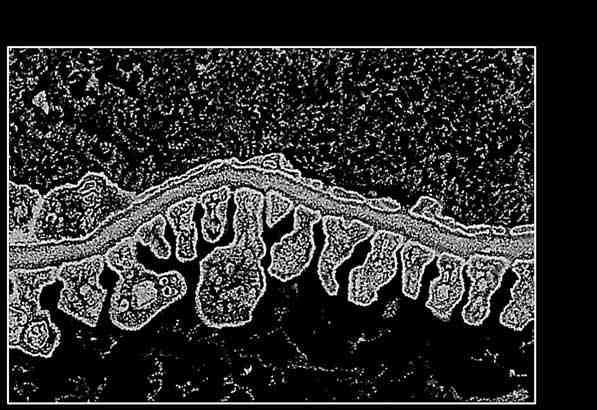

Рис. 7. Структура фильтрационного барьера почки; поперечный срез. Электронная микрофотография, увеличение 400x: 1 – просвет капилляра; 2 – поры; 3 – цитоплазма эндотелиоцитов; 4 – базальная мембрана; 5 – фильтрационные щели; 6 – цитоподии; 7 – полость капсулы нефрона

Из крови через этот барьер в просвет капсулы поступают жидкости и вещества, формирующие первичную мочу. Внутренний слой капсулы представлен эпителиальными клетками – подоцитами, которые располагаются на базальной мембране. Подоциты – это крупные клетки неправильной формы с широкими отростками. В течение суток в просвет капсул нефронов происходит фильтрация приблизительно 100 литров первичной мочи.